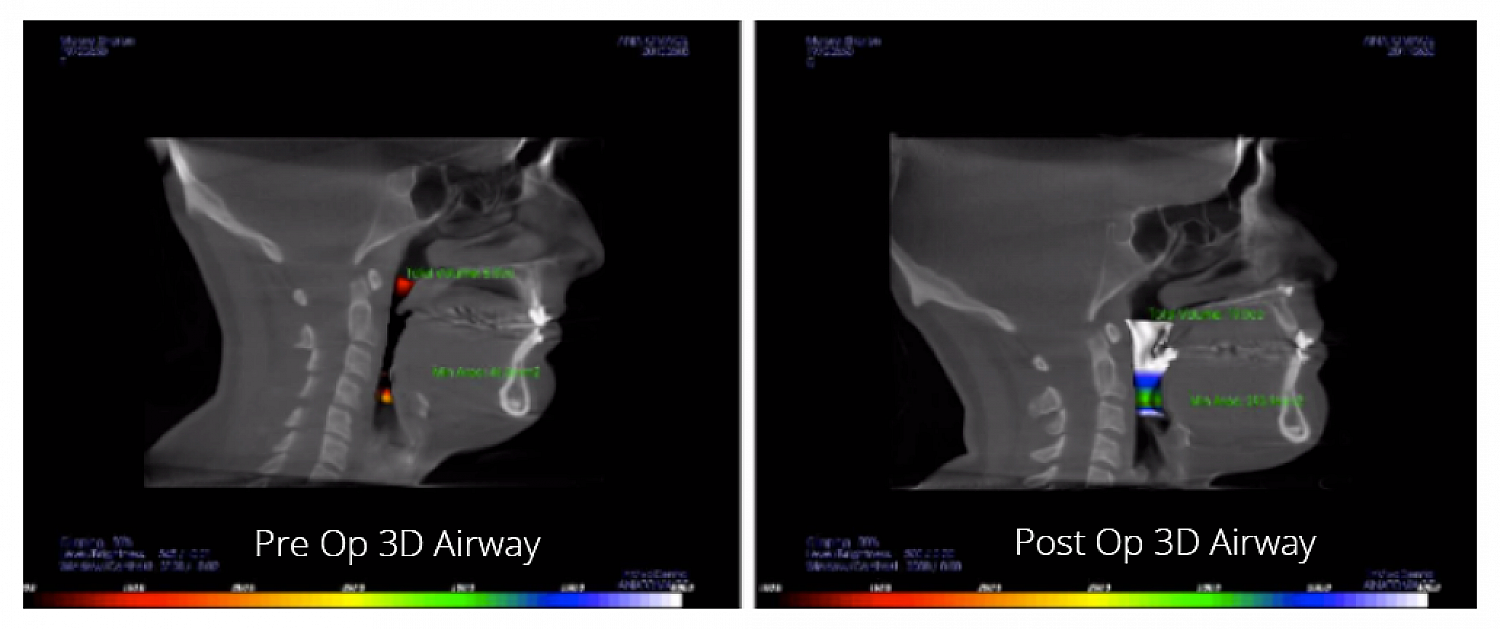

Pre-op and Post-op 3D Airway: Obstructive Sleep Apnea Surgery

Pre-operative and Post-operative 3D Airway Comparison

Bimaxillary advancement sleep apnea surgery, also known as maxillomandibular advancement (MMA), moves both the upper and lower jaw forward, creating a larger airway and eliminating obstructions that cause sleep apnea.